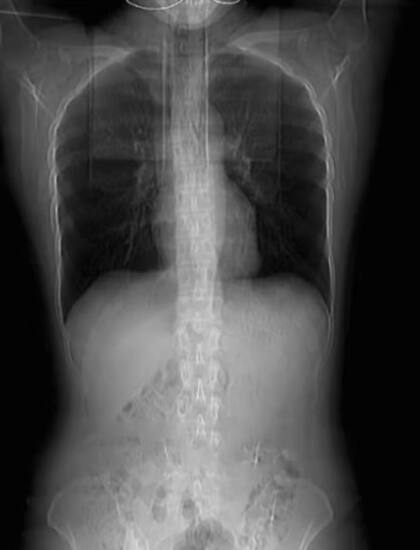

Horas más tarde, un dolor insoportable colmó la caja torácica de la mujer y una molestia interna le impidió respirar de manera normal, por lo que acudió de inmediato a un centro de salud para ser atendida por un profesional. Según informó Shanhai Video, le realizaron una radiografía a la paciente en la que el médico determinó que claramente sus cuatro costillas se fracturaron debido a la tos.

Este tipo de situaciones es poco común pero, puede suceder a menudo. El médico responsable de atender a Huang, le puso vendas alrededor de sus costillas y le aconsejó descansar durante un mes. Tiempo estimado para que logre sanar de manera correcta. “Tus costillas se pueden ver claramente debajo de tu piel. No hay músculo para sostener el hueso, por lo que es fácil que las costillas se fracturen al toser”, le remarcó el profesional a la mujer.

Con una altura de 171 cm y un peso de 57 kg, es evidente que Huang experimente este tipo de lesión en sus costillas, las cuales logran verse por sobre su piel. En tanto, la mujer damnificada prometió hacer ejercicio y alimentarse mejor para aumentar su masa muscular y así evitar la posibilidad de tener una fractura en otra parte del cuerpo.